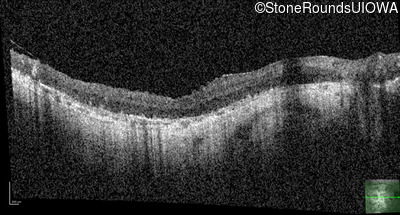

Optical Coherence Tomography - Left - Hand Motion sc

Exemplar / OCT Stack